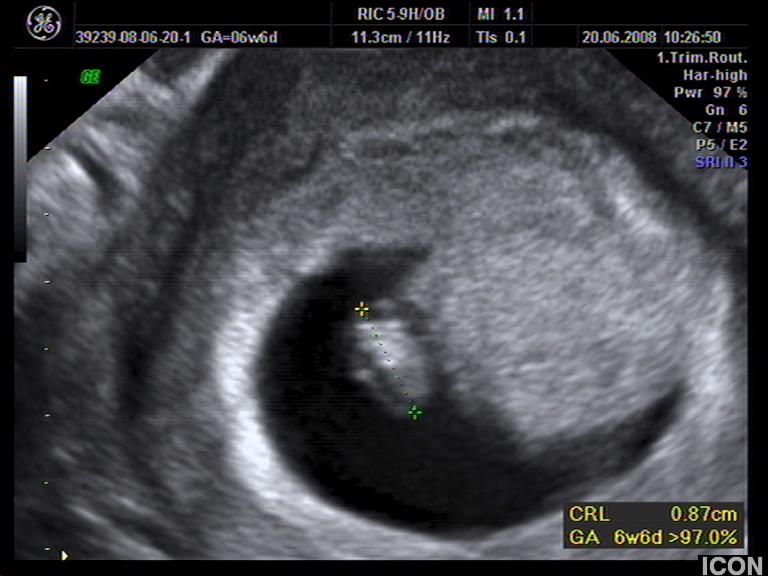

Αυχενική διαφάνεια

Η αυχενική διαφάνεια (ΑΔ) είναι η συλλογή υγρού στον τράχηλο του εμβρύου και συγκεκριμένα ανάμεσα στο δέρμα και στους ιστούς που καλύπτουν τη σπονδυλική στήλη.